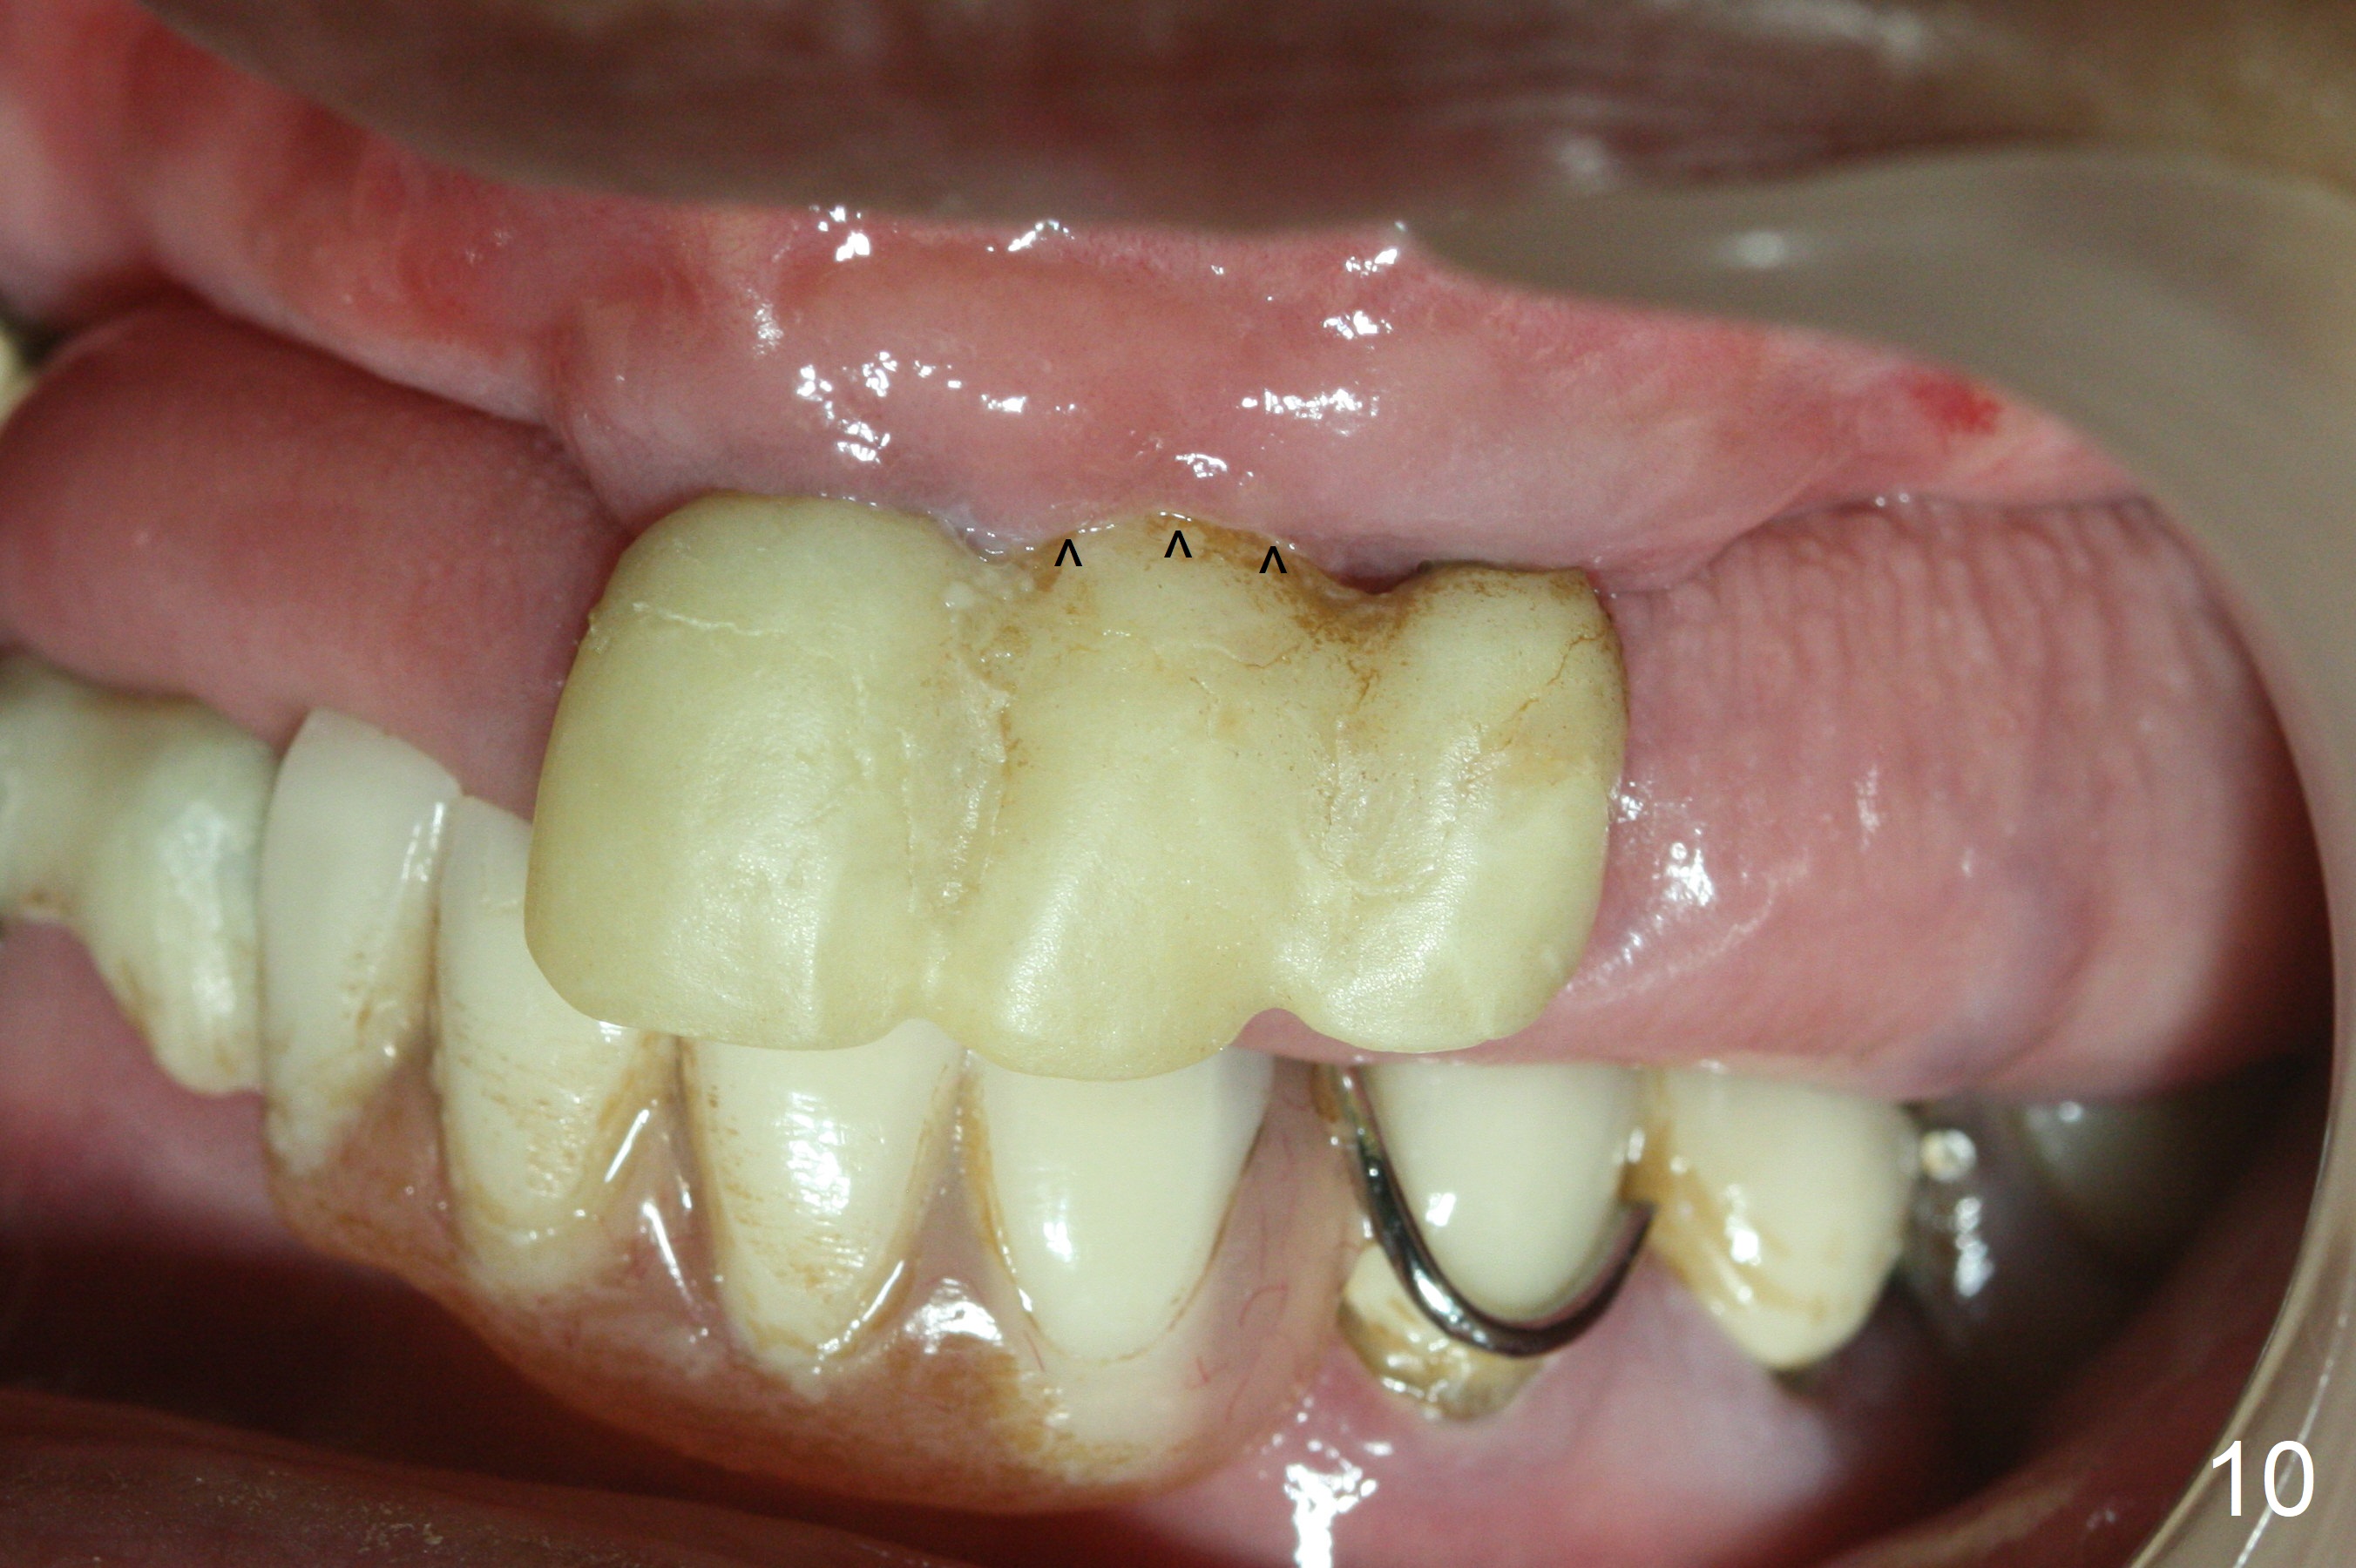

Incision reveals that the ridge at #9 and 11 is narrower than expected. A 3x14 mm 15º 1 piece implant is placed at the site of #9, while a 3x17 mm straight 1-piece one is placed at #11 (Fig.1,4). Insertion torques at #9 and 11 are 20 and 30 Ncm, respectively. The relatively low insertion torque is partially due to osteoporosis. The 65-year-old lady also has dry mouth. Osteotomy should be underprep. The position and trajectory of the implants are dictated by the partial denture (Fig.2). After minor abutment adjustment (Fig.3), an immediate provisional bridge is fabricated. There is no interference when the partial is removed and inserted. After bone graft (Fig.4 ^) and Osteogen Membrane, the ridge (Fig.3) is wider than before. The patient returns for reline 2 months postop (Fig.5-7). In spite of insufficient oral hygiene, the gingiva remains healthy around the implants. To form distinct papillae, acrylic should be added to (Fig.8 yellow line) and removed from (hushed area) the individual provisional crowns. One month after provisional modification (Fig.10, as compared to Fig.5), the pontic recipient site is concave (Fig.11) and becomes less concave after cord packing and abutment trimming. When the provisional bridge is reseated after impression (Fig.12), the pontic recipient site must be blanched again. Please trim the pontic recipient site of the model ~ .5 mm to enhance cosmetics. Water Pik has been used since surgery, but it may be related to loss of bone graft 3.5 months postop (Fig.9 *). One month post cementation, the patient has complained of pain when water pik is irrigating the gingiva palatal to the FPD, apparently in association with denture-related Candidiasis. Two weeks of use of Mycostatin Oral Suspension, peri-implantitis or peri-implant mucositis-like signs and symptoms disappear (Fig.13). CBCT taken 6 months postop confirms that the implants appear to be have been placed in the bone (14,15). The FPD appears to be loose 2.5 years post cementation.